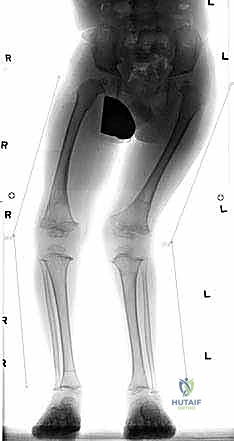

شكل 1 • أ. يعاني هذا الصبي البالغ من العمر 13 عاماً من السمنة والركبة الروحاء مجهولة السبب مع زيادة المسافة بين الكاحلين وعدم استقرار الرضفة. بدون تدخل جراحي دقيق لإعادة تنظيم الطرف، فإن التاريخ الطبيعي يشير إلى تدهور حتمي في وظيفة الركبة.

لا يكتمل التقييم السريري دون صور أشعة دقيقة. يطلب الدكتور هطيف صورة أشعة سينية طويلة للساقين بالكامل (من الورك إلى الكاحل) أثناء الوقوف (Standing Long-Leg X-rays). من خلال هذه الأشعة، يتم رسم خط المحور الميكانيكي، وحساب زوايا دقيقة جداً (مثل mLDFA و MPTA) لتحديد مركز التشوه بدقة متناهية، سواء كان في عظمة الفخذ، أو القصبة، أو كليهما.